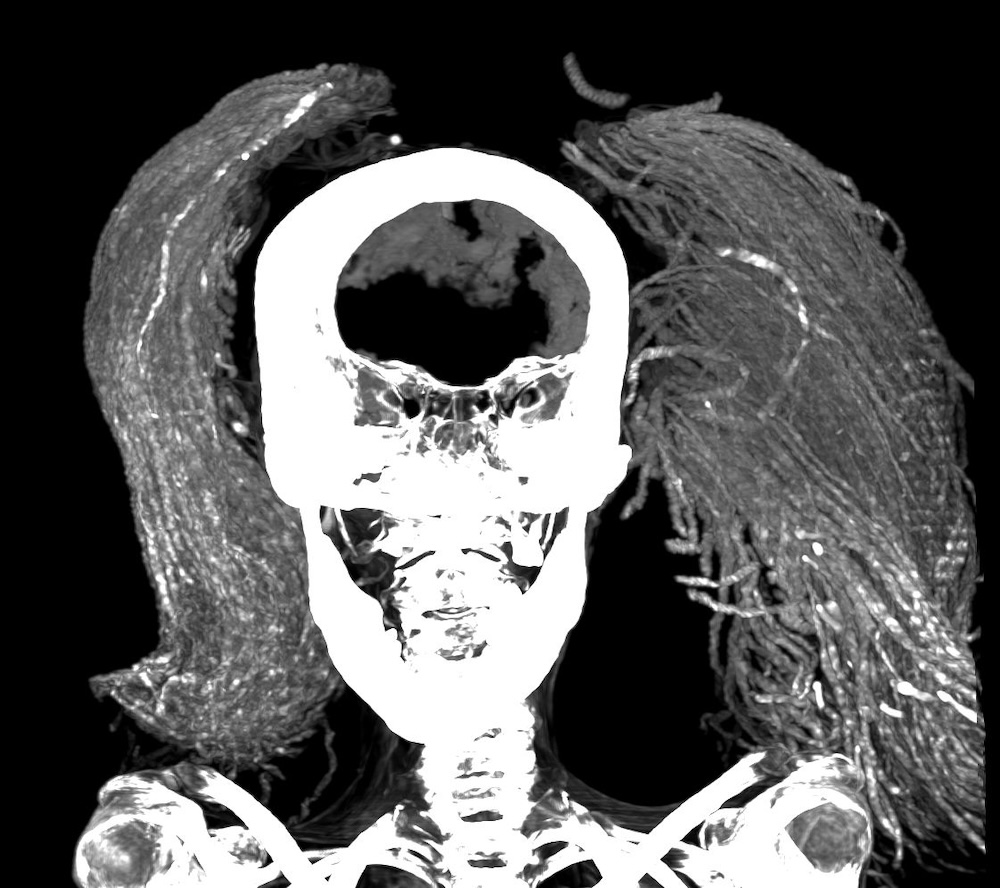

Radiology professor Sahar Saleem and colleagues at Cairo University’s Kasr Al Ainy Hospital have published a new study in the journal Frontiers in Medicine that provides never-before-seen, detailed looks at the mummy along with reliable theories about her health near the end of her life. Thanks to CT imaging, infrared spectroscopy, scanning electron microscopy, and other equipment, Saheer’s team theorize the open mouth may not be due to a shoddy burial, but rather the result of a cadaveric spasm in her final moments.

As for how she was prepared for mummification, Fourier transform infrared spectroscopy (FTIR) scans of the mummy’s skin revealed the presence of juniper and frankincense, luxuries that Egyptians would need to import from Southern Arabia, East Africa, or the Eastern Mediterranean. The woman’s natural hair was dyed with henna and juniper, but she also wore a long wig for the afterlife made from date palm fingers treated with albite crystals, magnetite, and quartz. These were often used to stiffen the wig’s locks and make them appear black to indicate a more youthful appearance.